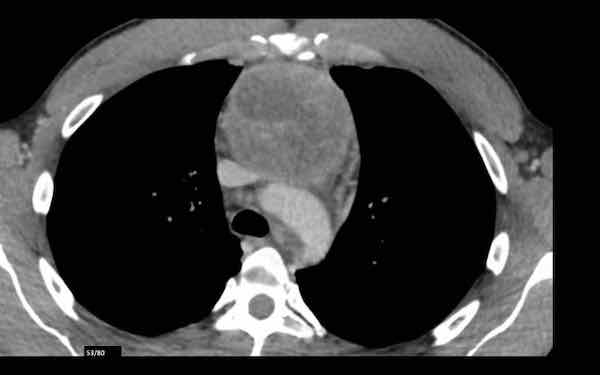

Các hình ảnh này của một phụ nữ 65 tuổi có tiền sử mắc bệnh Graves, một rối loạn tự miễn liên quan đến tình trạng cường chức năng tuyến giáp.

CT được thực hiện vì lý do ho ra máu.

Hình ảnh

Có một tuyến ức to lớn, cồng kềnh chứa mô mỡ đại thể.

Đây là hình ảnh điển hình của tăng sản tuyến ức.

Tăng sản tuyến ức trong bệnh Graves có liên quan đến tình trạng dư thừa hormone tuyến giáp và kháng thể kháng thụ thể thyrotropin.

Tình trạng này thường cải thiện sau khi điều trị thành công bệnh Graves.